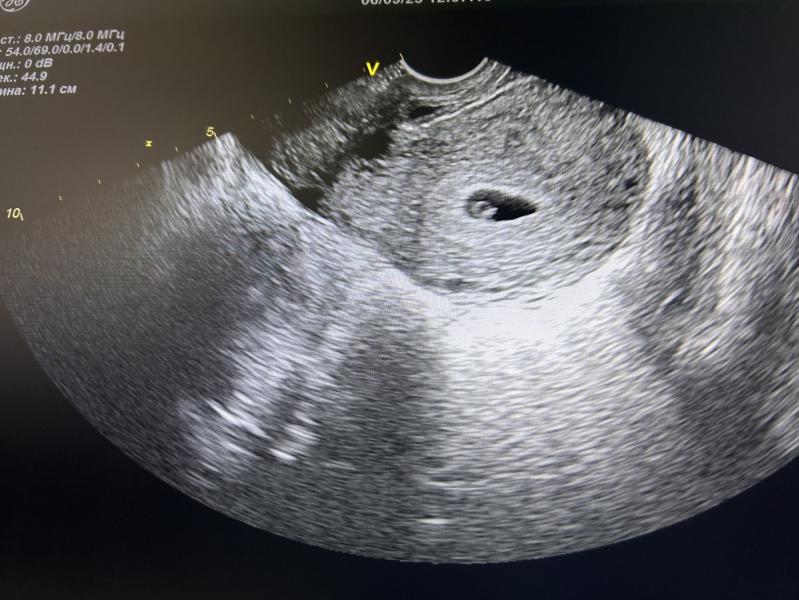

И сегодня на УЗИ эмбрион уже визуализируется(черная черточка в светлом желточном мешочке),сердцебиение есть. Желтое тело второй раз уже восторгает врача😅 по самочувствию не понятно,возможно появился токсикоз: иногда легкая тошнота( может и от голода), грудь чувствительна,иногда бросает то в жар,то в холод.

Так у меня же стоит срок) 6,3 н. 45 дц и 15 день задержки. Эмбрион соответствует сроку